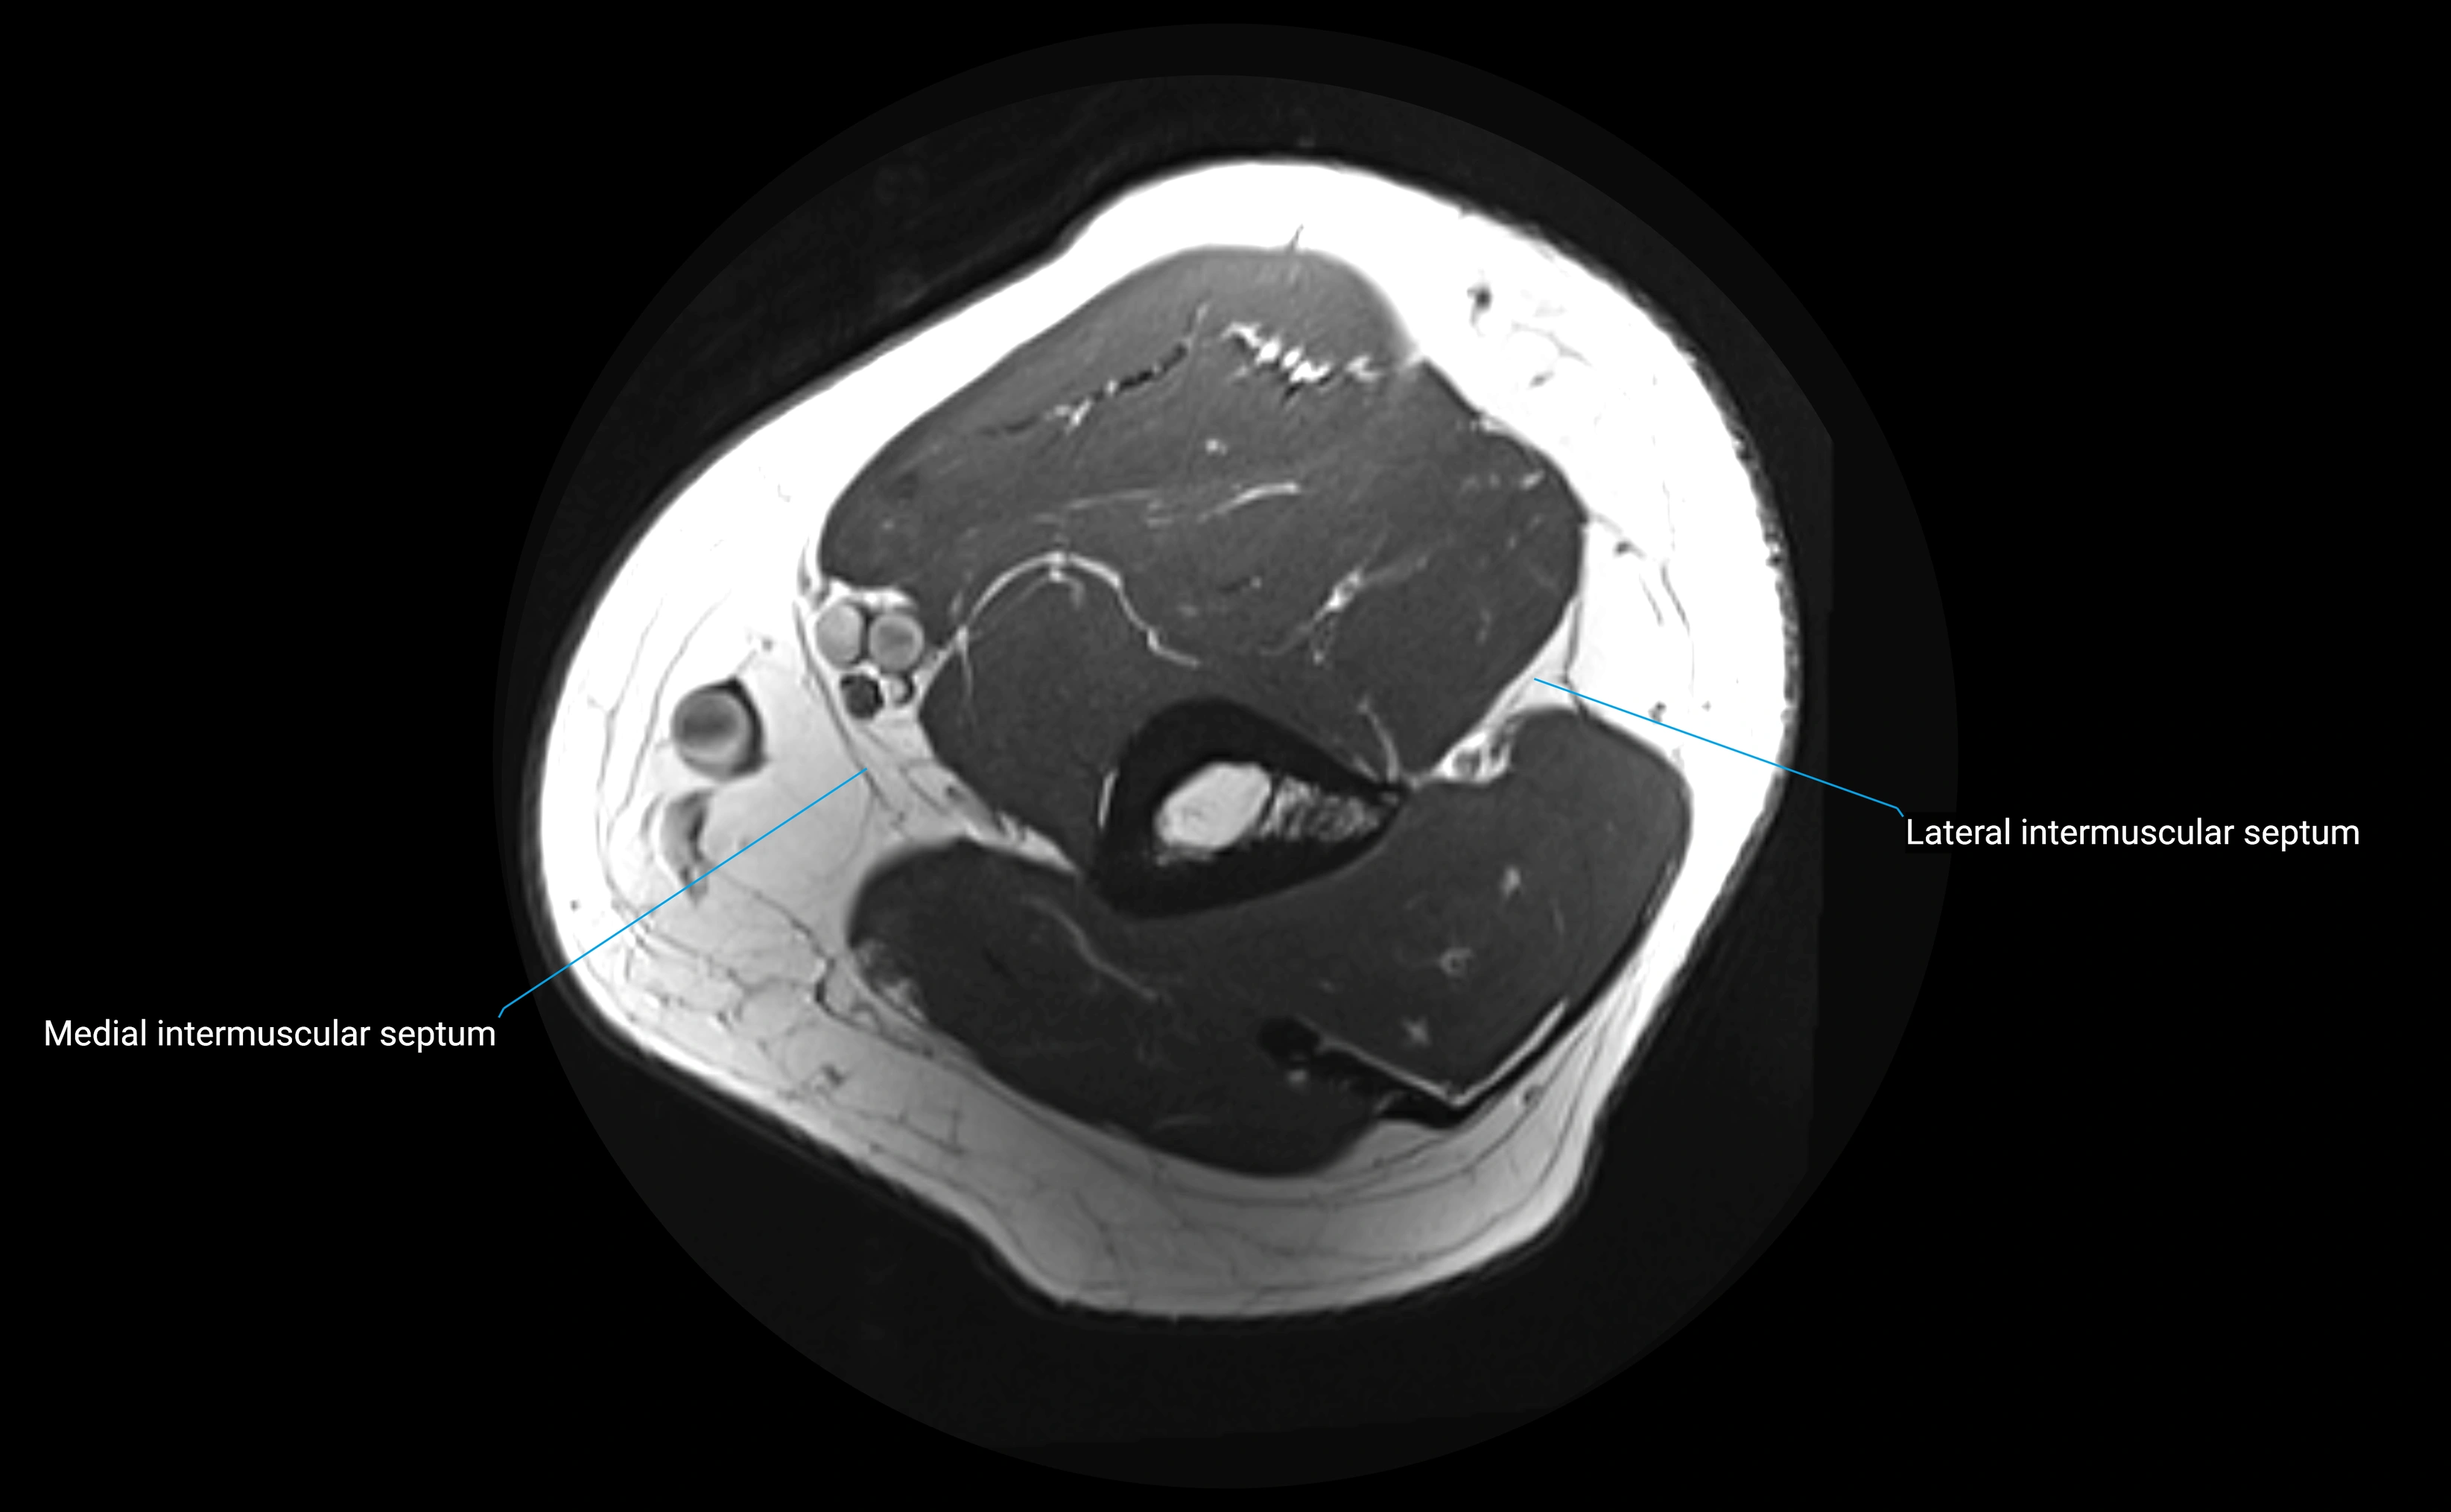

MRI images

image